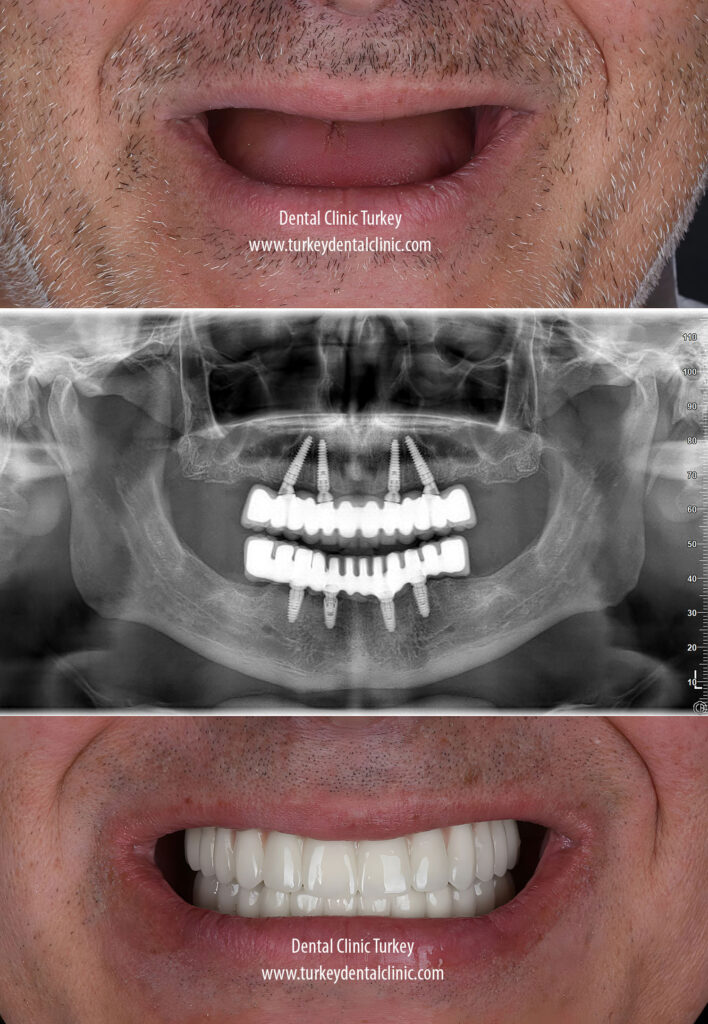

When patients visit our clinic in Antalya for a full-set dental implant procedure, we begin with a thorough examination, including a panoramic x-ray and a detailed oral assessment. Based on these evaluations, our doctors will develop a personalized treatment plan. Once the plan is in place, the implant surgery is performed to restore your smile.